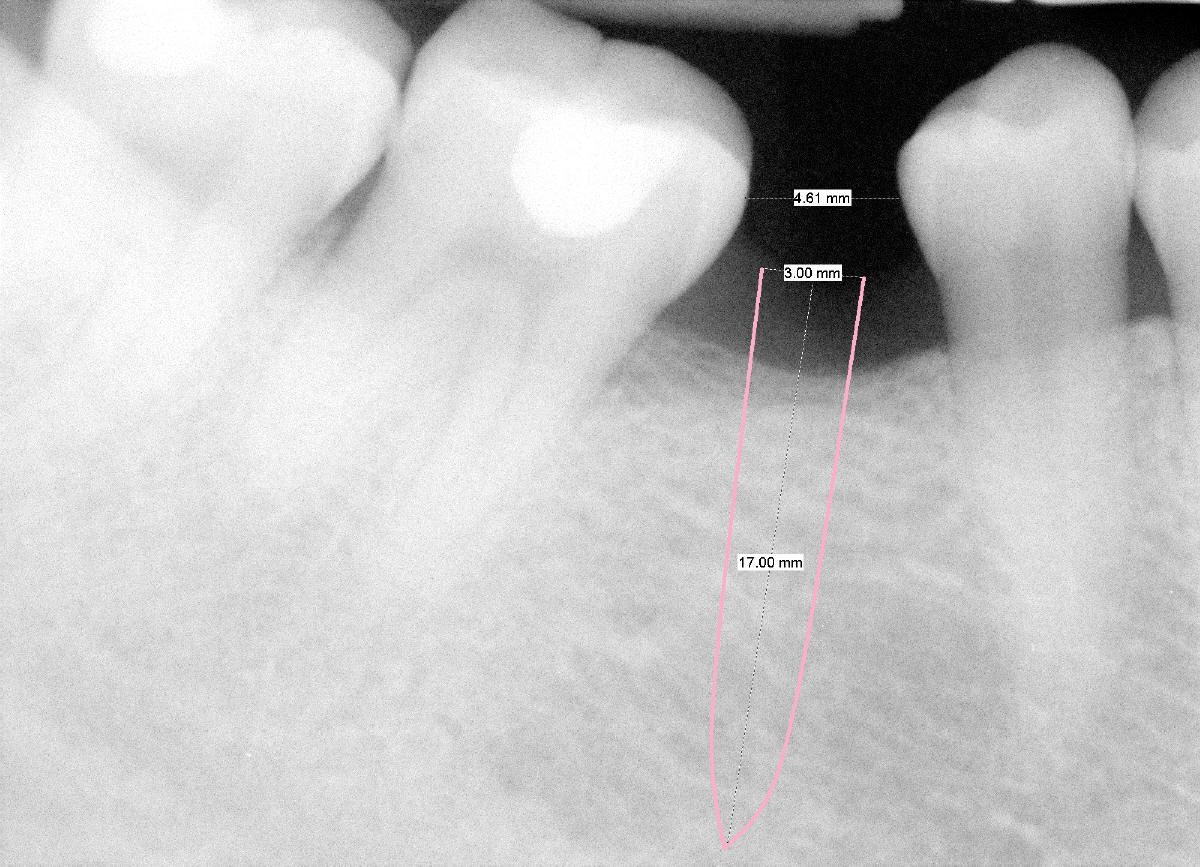

A 38-year-old lady has lost #30 for more than 20 years. She notices that the space has been narrowed and neighboring teeth have been shifted. She is thinking about fixing the space. Is a 3x17 or 20 one piece implant appropriate (Fig.)? Buccolingual occlusal table will be made narrow on crown.